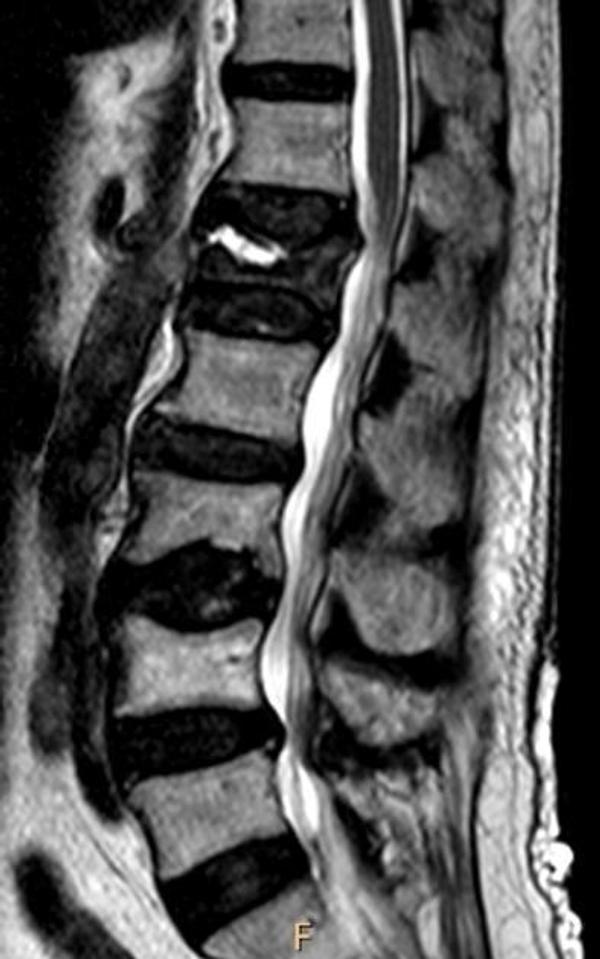

10. An otherwise healthy 50-year-old female presents with persistent axial low back pain after a fall 4 months ago. MRI lumbar spine is shown. What is your next best step in management?

Correct answer: DEXA scan

Explanation:

This patient has a vertebral compression fracture in the lumbar spine. The next best step would be to diagnosis osteoporosis with a DEXA scan. CT scan would not add any additional information at this time. Vitamin D level might be low but would not help you diagnose osteoporosis.